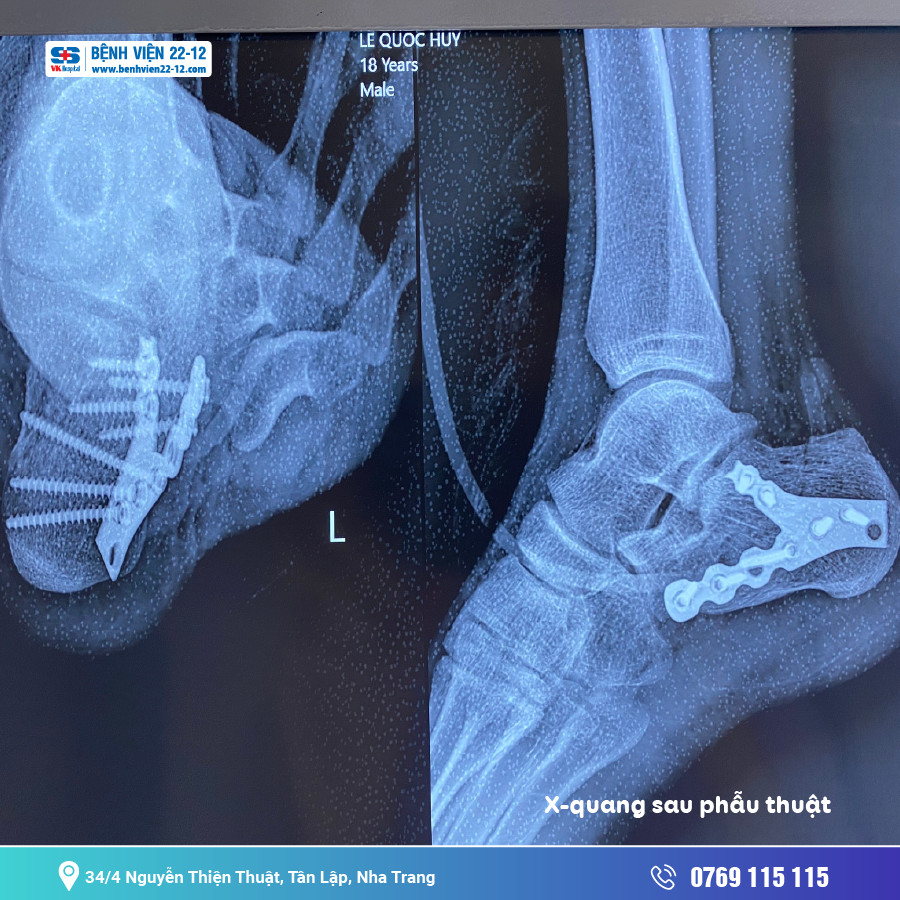

ThS BS Nguyễn Văn Tâm cho biết: “Gãy xương gót là một thương tổn nặng nhưng hiếm gặp, chỉ chiếm 1 đến 2% các loại gãy xương nói chung và khoảng 60% các gãy xương vùng cổ chân. Nguyên nhân đa phần do cơ chế nắn dọc trục làm cho xương gót phải chịu cả trọng lực cơ thể đè lên một cách đột ngột nên thường gặp là các hình thái gãy phức tạp xương gót, ảnh hưởng đên góc Bohler(Đánh giá diện khớp xương gót và xương sên). Gãy xương gót nếu không được chẩn đoán, đánh giá chính xác và điều trị kịp thời, chúng có thể dẫn đến những di chứng. Với công nghệ y khoa hiện đại, bác sĩ có thể chẩn đoán tình trạng gãy xương rất chính xác. Từ đó, áp dụng những phương pháp phẫu thuật phù hợp. Tuy nhiên vì đặc thù cấu trúc giải phẫu vùng gót chân nên việc phẫu thuật gãy xương gót phức tạp chưa bao giờ là dễ chịu với các phẫu thuật viên. Các Bác Sĩ lức nào cũng phải đối diện với các nguy cơ như: chết da vùng gót sau phẫu thuật, nhiễm trùng, lộ phương tiện kết hợp xương… Ngoài ra xương gót được cấu tạo từ võ xương cứng bao quanh bên trong là khối xương xốp nên khi gãy phức tạp sẽ gây khuyết xương sau nâng lún và thương phải lấy xương mào chậu ghép vào để nâng lún diện khớp và tăng tỷ lệ liền xương sau mổ.”